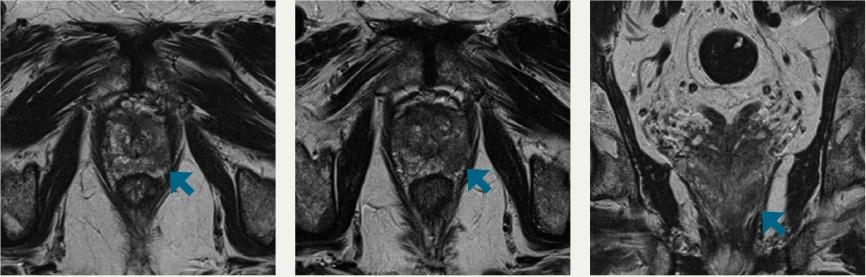

The majority of prostate cancers are classified as adenocarcinomas and originate in epithelial cells. The UTSW researchers initially determined that glucose stimulates release of the zinc ions from inside epithelial cells, which they could then track on MRIs. The prostate cancer tissue secreted lower levels of zinc ions, offering an opportunity to distinguish between malignant and healthy tissue. When they tested the technique on mouse models, they were able to successfully detect small malignant lesions as early as 11 weeks, making the non-invasive imaging procedure a potentially useful method for detecting the disease and its progression.

Typical MRIs do not reliably distinguish between zinc levels in healthy, malignant and benign hyperplastic prostate tissue, so discovery of the technique could eventually prove useful as a biomarker to track the progression of prostate cancer, according to researchers with the Advanced Imaging Research Center, part of UT Southwestern’s Harold C. Simmons Comprehensive Cancer Center.